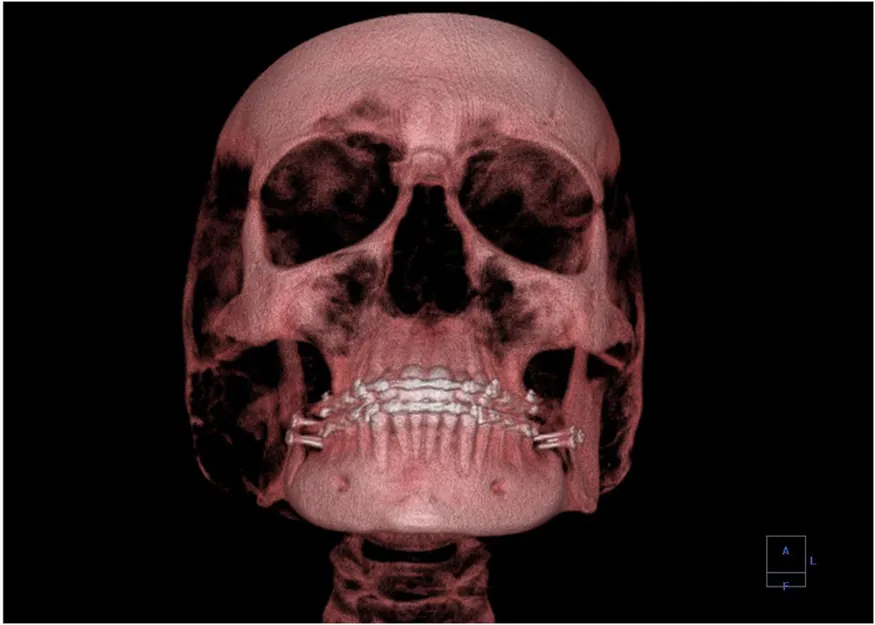

A 3-D image showing a human skull from the front.

Figure 30.28 This three-dimensional image of a skull was produced by computed tomography, involving analysis of several x-ray slices of the head. (credit: Emailshankar, Wikimedia Commons)